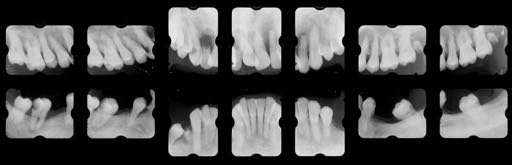

治療前